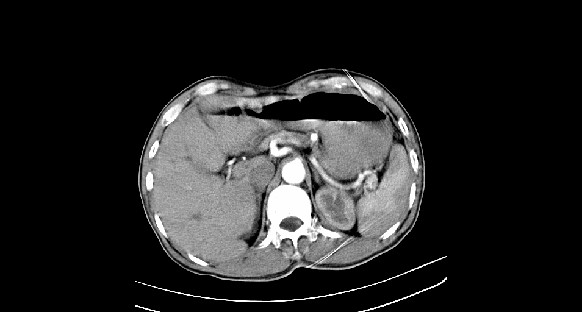

男性,70岁,体检b超发现左肾占位,请各位战友发表一下观点

左肾有两个病灶,且较大的病灶内可见点状钙化灶,增强扫描边缘也是呈渐进性强化,中央部分未见明显强化